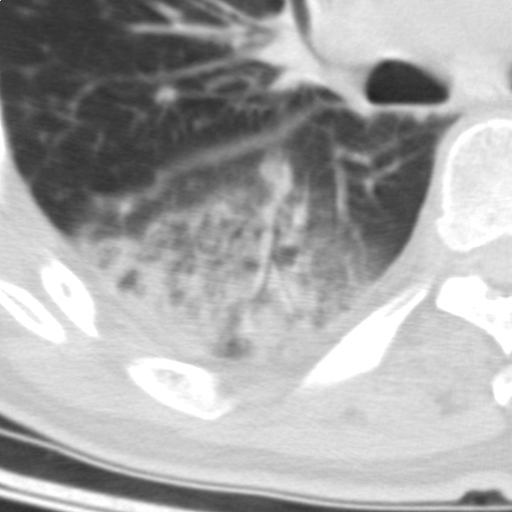

以下是引用随光逐影在2009-5-1 13:53:00的发言:[br]考虑为:1)两肺血行播散型肺结核;2)右肺下叶炎症感染。3)右侧胸膜增厚。